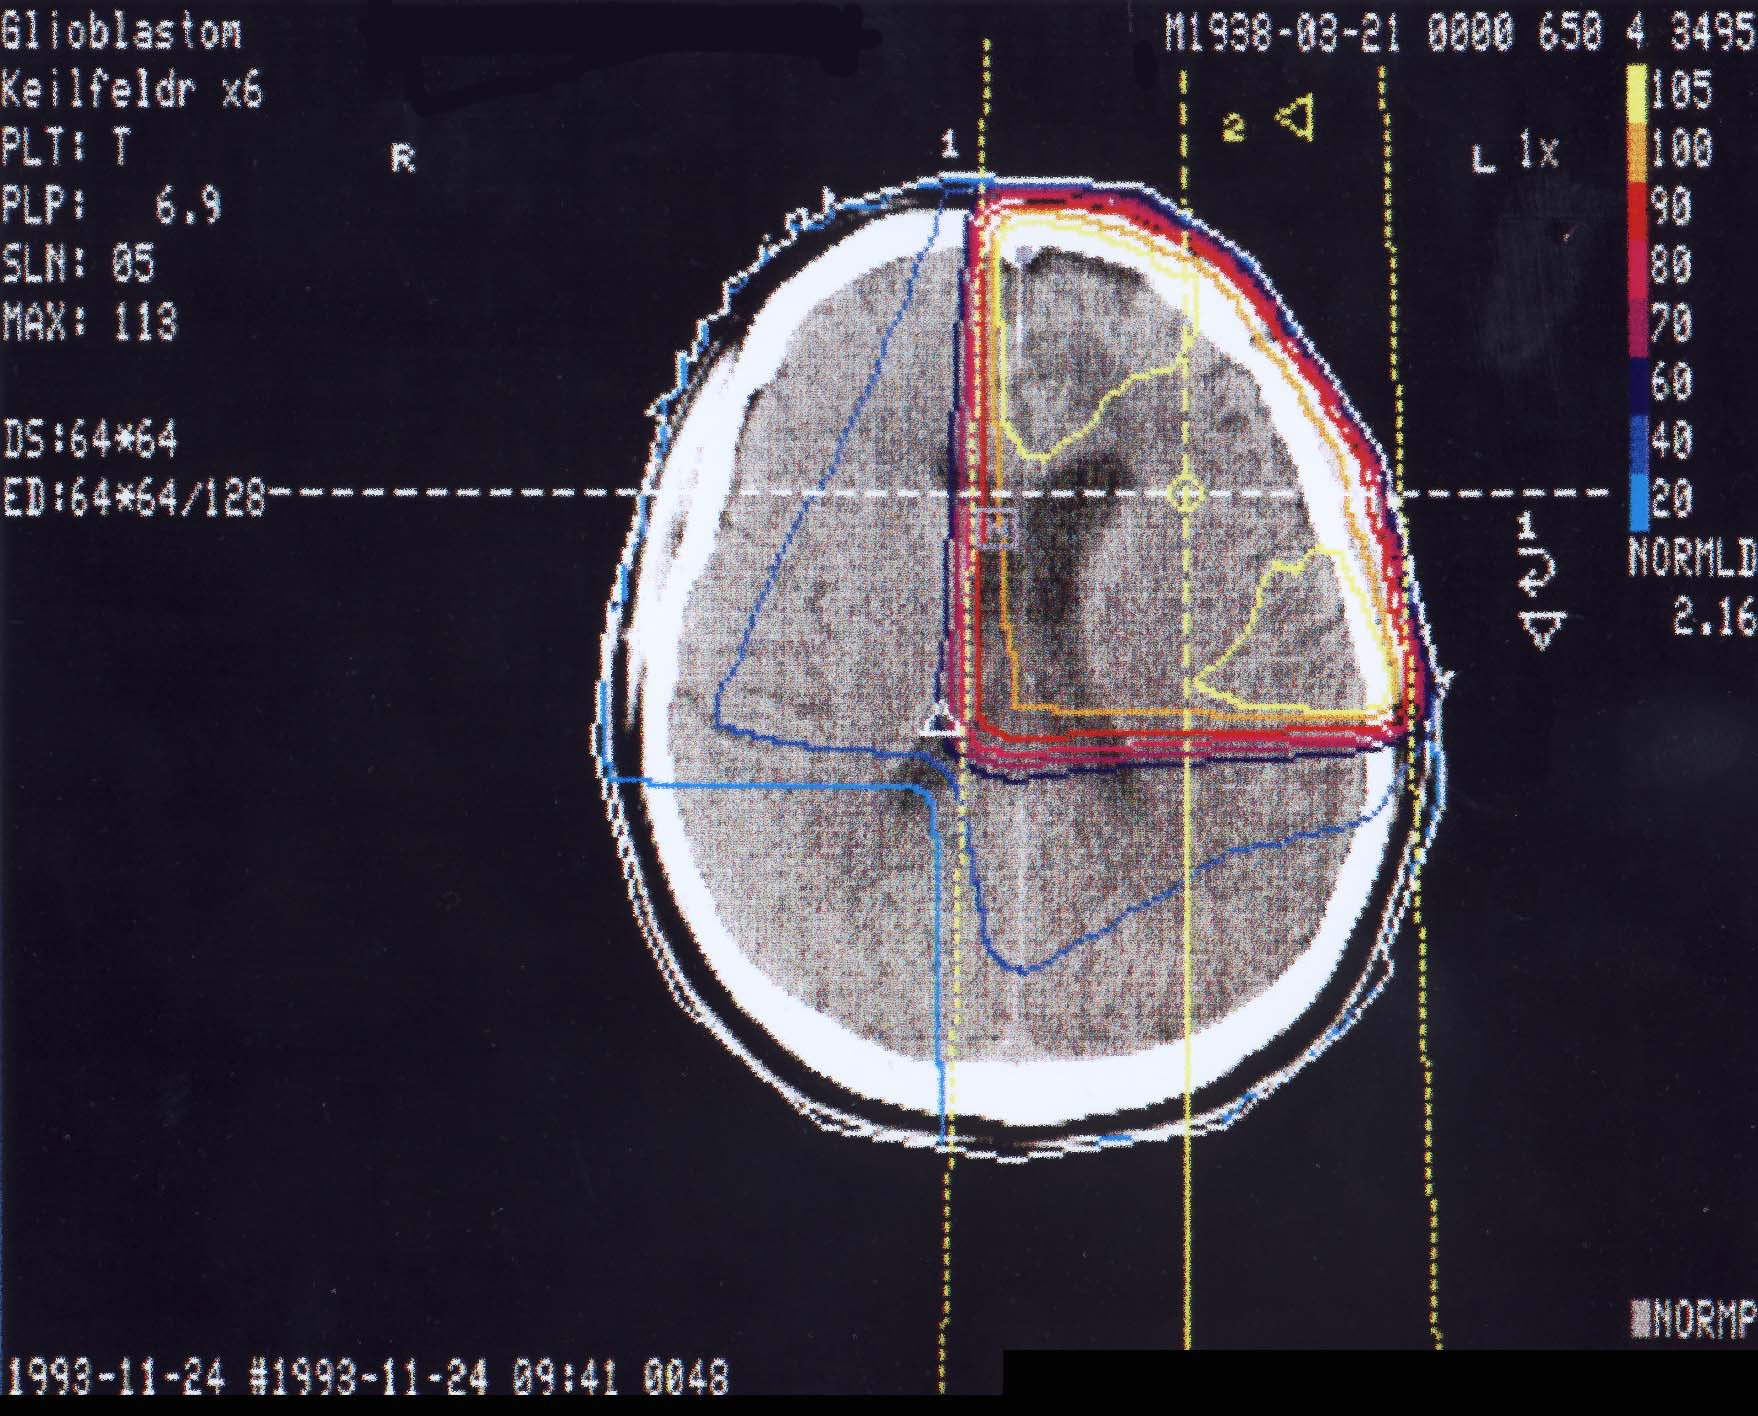

Hirntumore: Bestrahlungsplan

Einführung aktuelle Bilder - Einführung Bestrahlungspläne - Einführung Demonstration